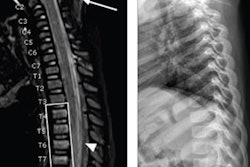

According to the results, out of 2,081 patients with negative x-rays, 1,974 (95%) had their c-spines cleared without additional imaging. The remaining 108 patients had additional c-spine imaging after negative c-spine x-ray for c-spine clearance (24 CT, 76 MRI, and 8 both CT and MRI). Indications for additional c-spine imaging were pain (48.1%), a GCS score ≤ 14 (43.5%), and paresthesia (8.3%), the researchers reported.

“In this cohort, screening [x-ray] had a sensitivity of 100% for clinically significant c-spine injuries,” they wrote.